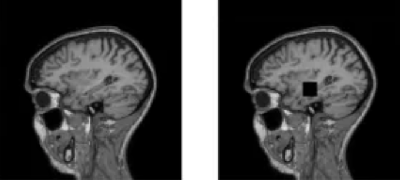

Разработка, генерирующая и анализирующая синтетические МРТ-снимки головного мозга, предназначена для специалистов медицинских информационных технологий, кроме того, платформа позволяет обучать нейросетевые модели.

Почему это важно и нужно? У современных ИИ-разработок в области медицины есть один нюанс – законодательные и этические нормы ограничивают доступ к МРТ-данным для обучения и валидации систем диагностики. Реальные данные недоступны, а стандартные генеративные модели, хотя и правдоподобные, но некорректные. В настоящее время инструмента, который сочетал бы точную разметку, этическую безопасность и давал бы возможность задавать тип, локализацию и выраженность патологий, не существует.